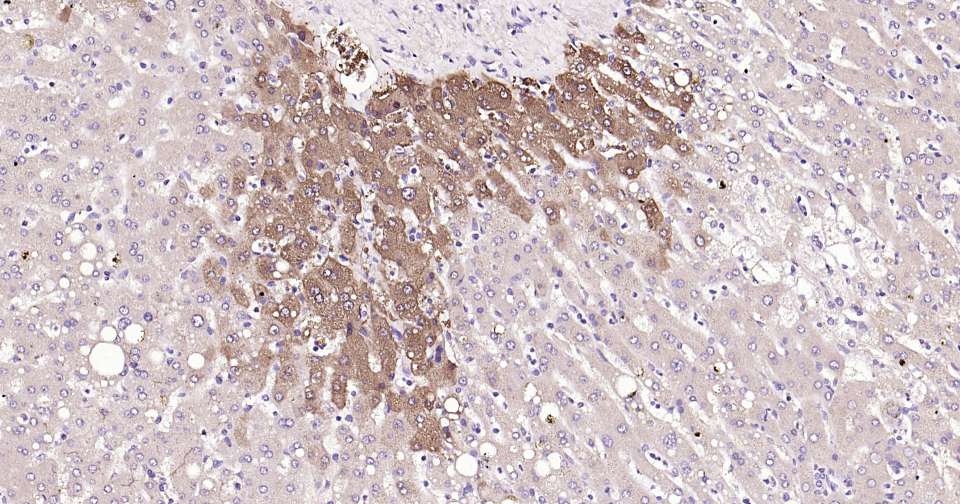

Immunohistochemical analysis of paraffin embedded human liver tissue slide using IHC0333H (Human Glutamine synthetase Kit).